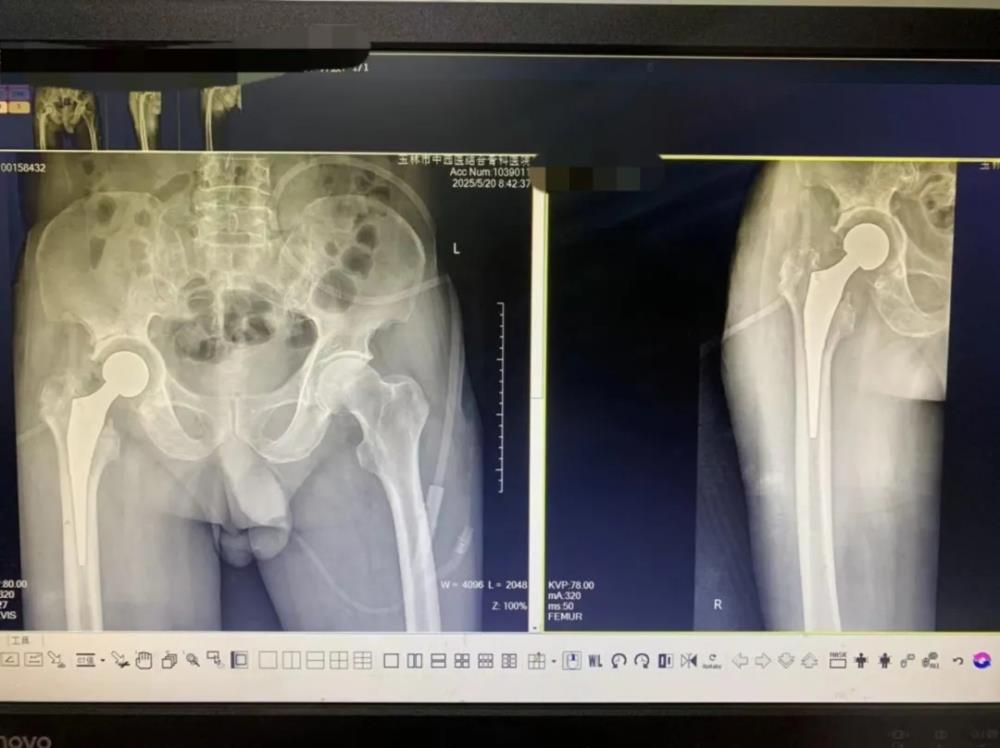

术后DR